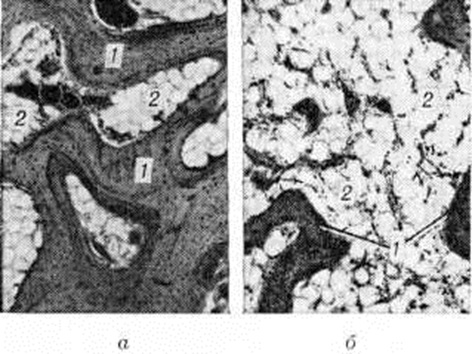

Развитие деоссификации при Остеопороз обусловлено снижением костеобразования и усилением резорбции кости (смотри полный свод знаний), что приводит к расширению каналов остеонов (гаверсовых каналов). В результате Остеопороз корковое вещество кости утрачивает компактное строение, спонгизируется (рисунок 1). Костные перекладины губчатого вещества истончаются, часть их рассасывается полностью, что приводит к расширению пространств между ними (рисунок 2). Разрежение губчатого вещества с уменьшением общего числа костных перекладин и количества минеральных веществ в единице объёма кости нередко сочетается с одновременным утолщением и огрубением сохранившихся костных перекладин. Такая перестройка особенно часто встречается при анкилозе сустава.